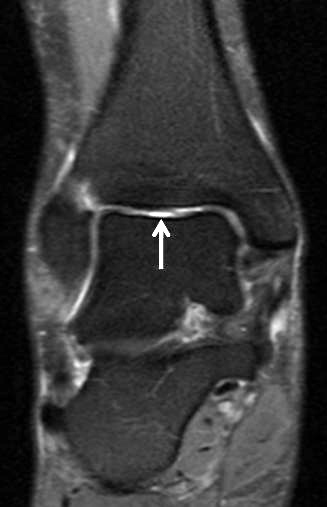

Jedoch findet man sich auch hier mit dem Problem der in den Standard-Projektionen schräg verlaufenden Syndesmose konfrontiert. Der oligofaszikuläre Aspekt der vorderen Syndesmose kann in der axialen Schnittebene eine zum Verwechseln ähnliche Morphologie wie eine Ruptur aufweisen (Abb. 15 b und c). Doppelangulierte Schnitte entlang der Achse (schräg koronar/schräg sagittal) lassen hingegen eine eindeutige Beurteilung der Bandstrukturen zu (Abb. 16) und verbessern die Syndesmosendiagnostik.

Bezogen auf die Transversalebene verläuft die Syndesmose ca. 30° schräg cranio-caudal anguliert (Abb. 15 a). Häufig lassen sich drei Hauptfaszikel differenzieren: das kürzeste superiore, das stärkste mittlere und das längste kaudale Faserbündel. Ein akzessorisches Bündel, das anteriore-inferiore, tibiofibulare Ligament (AITFL) oder auch Bassett-Ligament wird in 80-94% der Patienten nachgewiesen 8. Dies weist einen unmittelbaren Bezug zur anterolateralen Talusschulter auf (Abb. 17). In Kombination mit einer Außenbandinstabilität und konsekutivem, talarem Vorschub kann dieses zu einem Impingement an der anterolateralen Taluskante führen mit nachfolgender chondraler oder osteochondraler Läsion.